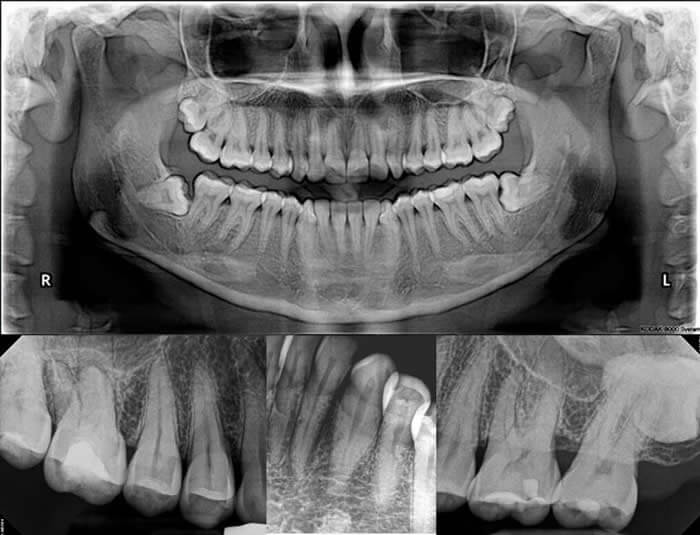

Extracción de muelas del juicio

Una de las intervenciones más comunes en cirugía bucal es la extracción de las muelas del juicio.

Se recomienda cuando:

- No hay espacio suficiente para su erupción.

- La dirección de salida es incorrecta y puede dañar la muela anterior.

- Causan malposición en el resto de dientes.

Caninos incluidos

En algunos casos, los caninos (colmillos) no erupcionan correctamente y quedan incluidos en el hueso.

Puede ser necesario:

- Extraerlos, si presentan quistes asociados.

- Exponerlos en boca y traccionarlos mediante ortodoncia para guiarlos a su posición correcta.